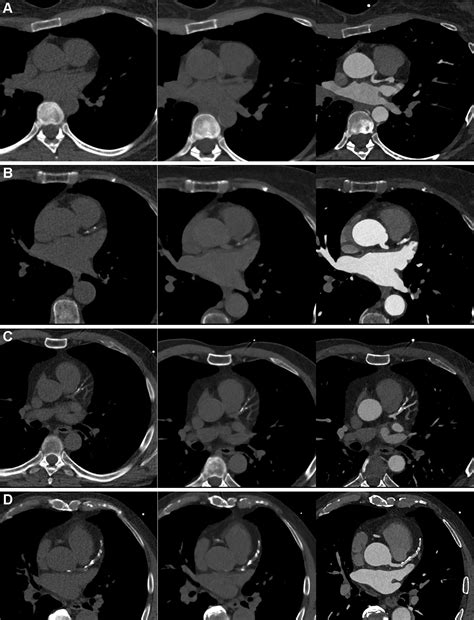

Coronary Artery Calcium scoring is a specialized type of computed tomography (CT) scan that focuses on the heart. Unlike traditional CT scans, CAC scoring specifically looks for calcium deposits in the coronary arteries. These deposits are a sign of atherosclerosis, a condition where plaque builds up in the arteries, narrowing them and increasing the risk of heart attacks and strokes.

During a CAC scan, the patient lies on a table that slides into a CT scanner. The scanner takes multiple X-ray images of the heart from different angles. A computer then processes these images to create a detailed picture of the coronary arteries. The amount of calcium in the arteries is measured and given a score, known as the Agatston score.

• Radiation Exposure: The test involves exposure to a small amount of radiation, although the risk is generally considered low.